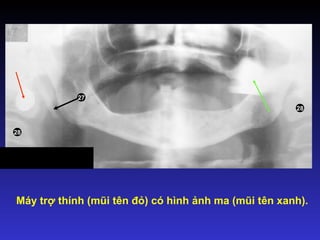

Hình ảnh ma

Thường là hình ảnh của các vật

thể ngoại lai nhưng cũng có thể

là hình ảnh của cấu trúc giải

phẫu nào đặc như cấu trúc của

xương hàm dưới.

Bóng của vật thể cản quang

nằm bên đối diện (khuyên tai,

cấu trúc giải phẫu nào đó)

Đặc điểm của hình ảnh ma:

 Nằm bên đối diện

 Cùng hình dạng

 Phóng to hơn

 Nằm cao hơn

 Mờ hơn

Hình ảnh ma của khuyên tai

15 2

Máy trợ thính (mũi tên đỏ) có hình ảnh ma (mũi tên xanh).

27

28